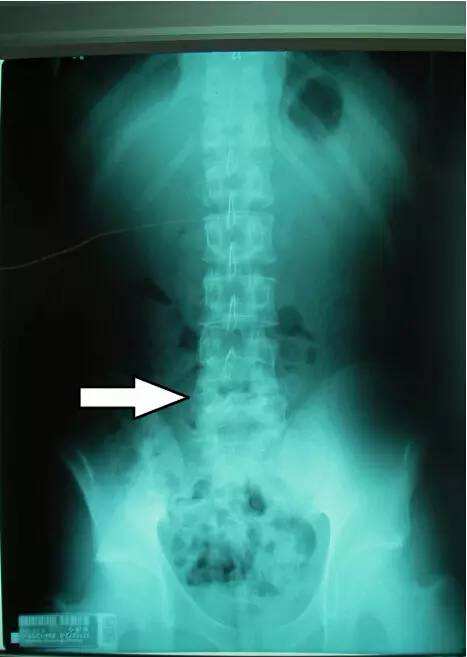

强直性脊柱炎的英文名称是ankylosing spondylitis,Marie- S ...